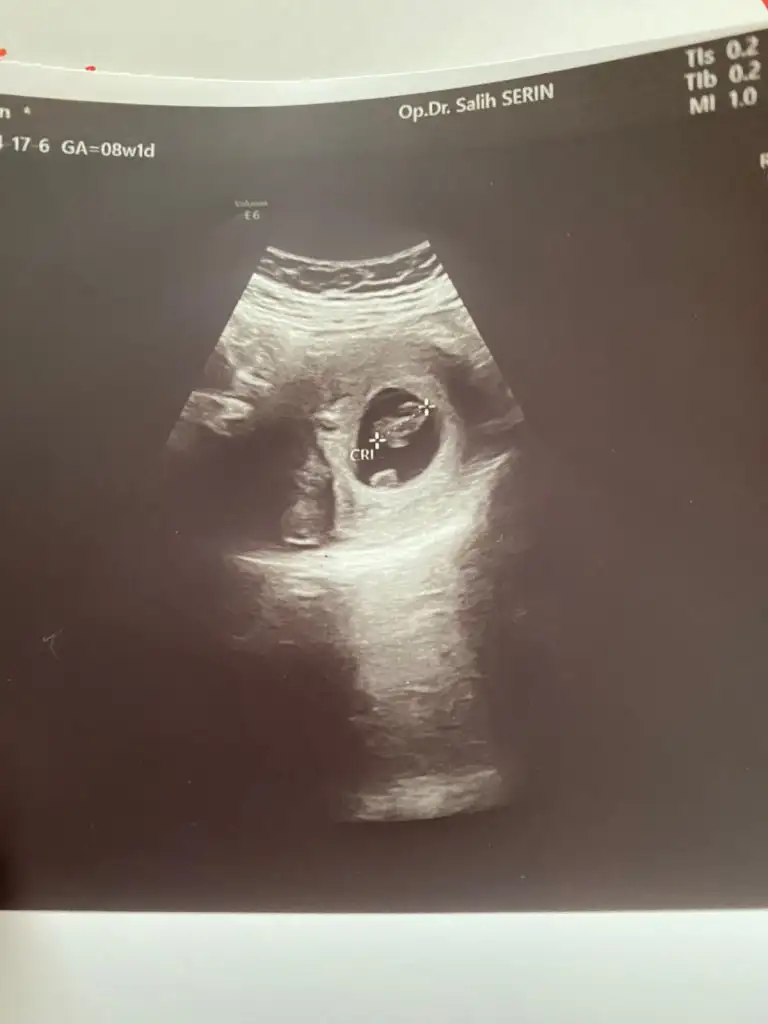

Ramzi Teorisi ve cinsiyet tahmini ( tutma olasılığı %85 miş )

Kızına kız arkadaş geliyor gibi dedi ama haftayi bekleyelim dedi bende dedim ama ilk görüntüsünde sağa yerlesmis dediniz dedim haftaya daha sağlıklı olur bakalım dedi ikrameyra

Hayırlısı olsun cnm bakalım değişicekmi

IMG_20200323_220215.webp